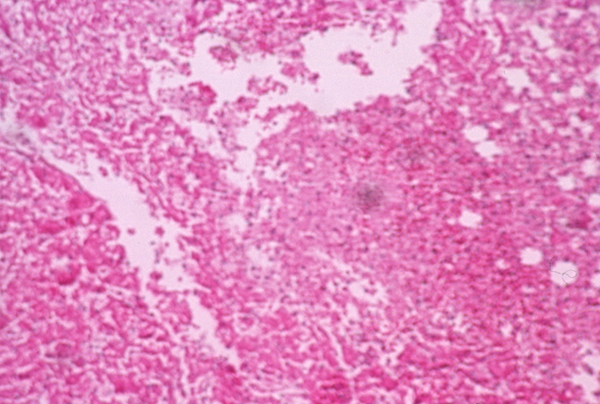

017